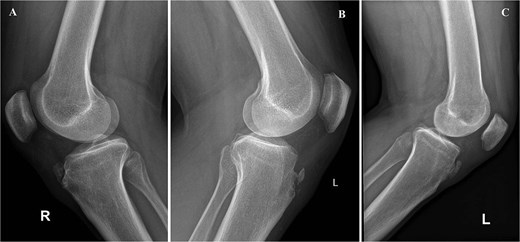

On physical exam, they had localized tenderness at the tibial tubercle, pain when kneeling, and discomfort with resisted knee extension. X-rays showed persistent ossicles in all cases, and we followed up with MRI to rule out any other underlying issues (Fig. 1).

Preoperative lateral radiographs showing persistent tibial tubercle ossicles. (A) Right knee for first case. (B) Left knee for second case. (C) Left knee for third case.